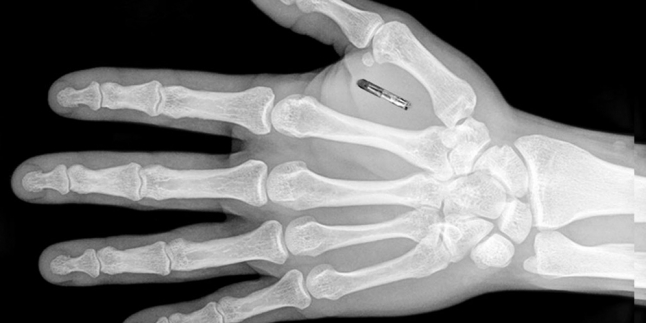

BioNyfiken memulai penelitian chip implan sejak 2013. Chip yang terbuat dari kaca ini pertama kali ditanam di tubuh manusia pada Oktober 2014. Chip ini berukuran sebesar butir beras, dan dapat ditanamkan di tangan, tepatnya di antara ibu jari dan telunjuk. Tak perlu takut rasa sakit sebab BioNyfiken sudah menguji coba ke 100 orang.

BioNyfiken memunculkan penemuan mereka acara Cyber Security Summit Apac 2015 di Port Dickson, Negeri Sembilan, Malaysia akhir pekan lalu. Chip ini menggunakan teknologi Near Field Communication (NFC) dengan spesifikasi 2x2 mm glass-encapsuled passive 13.56 MHz NTAG216 Chip, sehingga chip dapat berkomunikasi dengan segala alat yang juga memanfaatkan NFC.